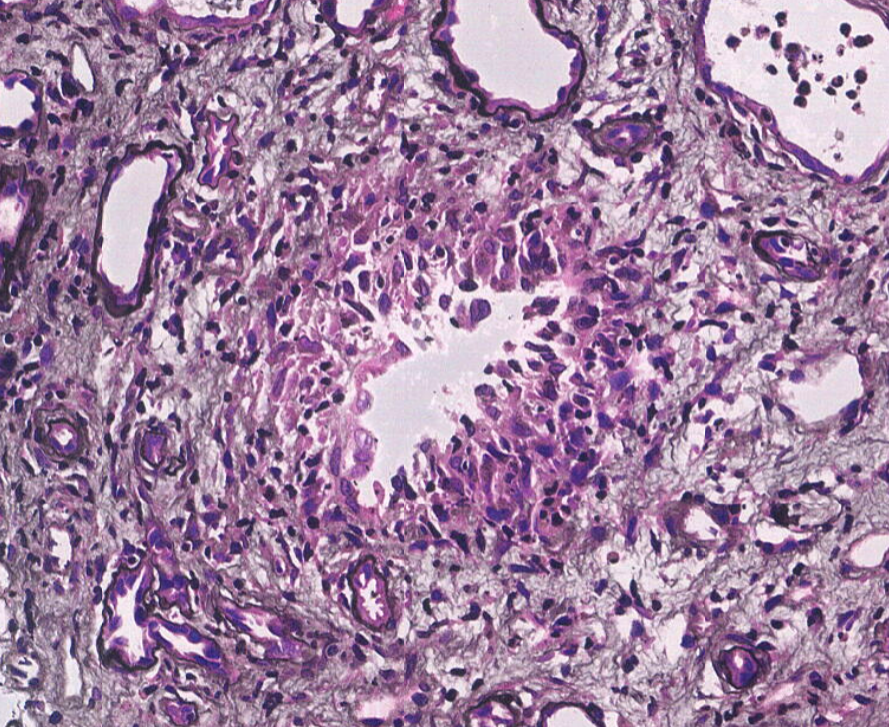

Unfortunate but not rare IgAN presentation. Pt in their 30's, no PMHx, presented with HTN emergency, CKD, hematuria, proteinuria. Advanced IgAN with severe IFTA, focal active crescents (M1 E1 S1 T2 C1). Wish we could catch these cases earlier. #renalpath #pathtwitter #nephrology